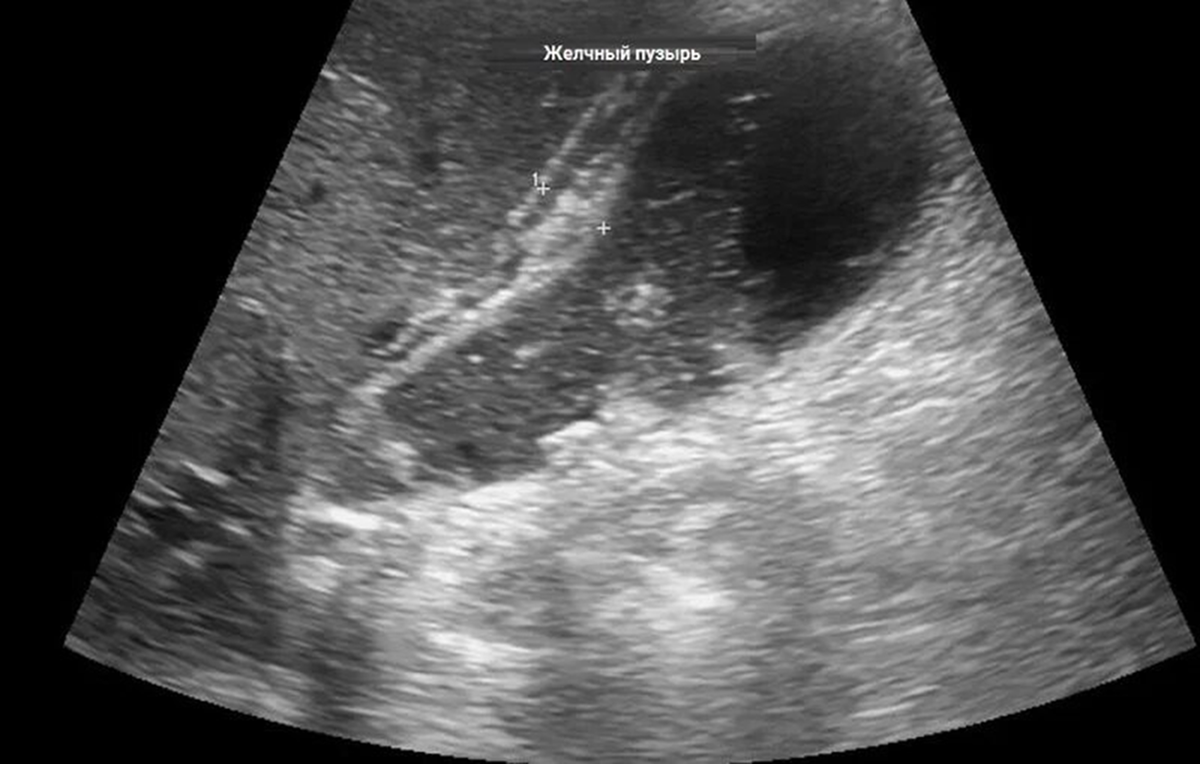

ОСТРЫЙ КАЛЬКУЛЁЗНЫЙ ХОЛЕЦИСТИТ - острое воспаление желчного пузыря, одно из наиболее частых осложнений желчнокаменной болезни (каждые пять лет количество пациентов в мире удваивается). Боли в точке Кера. Что необходимо запомнить пациенту. Дело в том, что если у пациента уже подтверждённая желчнокаменная болезнь и имеет место нарушение диеты питания (приём жирной, острой, солёной пищи) - желчный пузырь может сократиться с вклинением камня в пузырном протоке. Хуже если камни мигрируют дальше в общий желчный проток и ущемятся в Фатеровом сосочке. Тогда возможны сильные боли в правом подреберье, потрясающий озноб и механическая желтуха (триада Шарко - проявление ОСТРОГО ОБТУРАЦИОННОГО ХОЛАНГИТА - воспаления желчных протоков вследствие проникновения в них инфекции из желчного пузыря, кишечника, кровеносных сосудов или по лимфатическим путям). Ещё один немаловажный нюанс. Если после сильного приступа боли прошли, но при ультрасонографии определяется увеличенный желчный пузырь, утолщение стенки желчного пузыря более 3 мм, перивезикальный отёк и камни в желчном пузыре - значит стенка превратилась в гангренозную (поэтому и боли прошли). Тем более надо срочно оперировать, так как в последующем желчный пузырь может перфорировать (гангренозно-перфоративный холецистит) и операция усложнится значительно. Лапароскопическим способом после трёх суток приступа не всегда получается удалить желчный пузырь.

Речь идёт об осложнении ЖЕЛЧНОКАМЕННОЙ БОЛЕЗНИ - ХОЛЕДОХОЛИТИАЗЕ, ОСЛОЖНЁННОМ ОСТРЫМ ГНОЙНЫМ ХОЛАНГИТОМ (триада Шарко - проявление ОСТРОГО ХОЛАНГИТА - воспаления желчных протоков вследствие проникновения в них инфекции из желчного пузыря, кишечника, кровеносных сосудов или по лимфатическим путям). На самом деле понять суть заболевания не сложно. Желчь вырабатывается в печени, поступает по желчевыводящим протокам в двенадцатиперстную кишку через Большой дуоденальный сосочек (Фатеров). Надо помнить, что особенно опасны камни менее 4 мм - они чаще могут мигрировать через пузырный проток (проток от желчного пузыря) в общий желчный проток. И далее ущемляться в Фатеровом сосочке. При фиброгастродуоденоскопии это выглядит так: